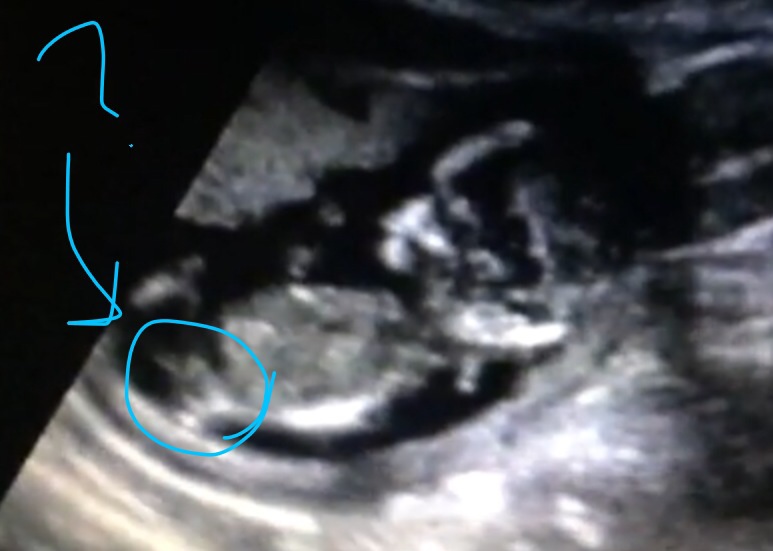

Is this a nub? Or can you see it. Lol. I'm obviously not an expert!

13+4, measuring 13+6! Thank you all!!